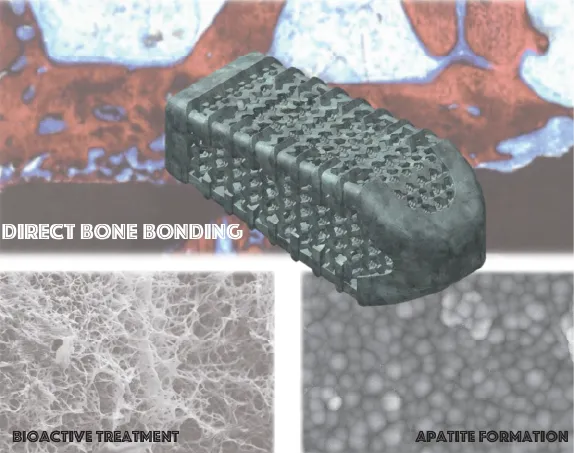

X-TAL

2018年に薬事承認を取得した低侵襲腰椎側方固定用の人工骨です。自家骨を採取せずに手術が可能になったため、低侵襲の手術が可能になりました。すでに日本全国で多くの患者さまの治療に用いられています。

低侵襲腰椎側方固定用人工骨:X-TAL

-

骨と人工骨の結合